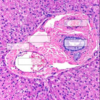

Enzymes Indicating Cholestasis

(2)

- we have lots and lots of hepatocytes, can see increases with little or large damage

- key enzymes of cholestasis: ALP and GGT

Alkaline Phosphatase

(ALP)

Derived from bile duct epithelium

- cholestasis will irritate bile duct epithelial cells and this ALP will be released

- but it also comes from other places too (young dogs- bone isoform of ALP) –> need to be aware

- any dog that is stressed or given prednisolone over time will likely have a notable ALP increase (steroid induced isoform)

- in cats it has a VERY short half life, any increase is significant (could be hepatic lipidosis, or if not yellow- hyperthyroidism) –> the dynamic of the changes can be very important in cats

- dogs can get an increase for stress and other things

Induction vs. Leakage

ALP is an induction enzyme: they are present on some of the biliary epithelium but can also have induced production of these enzymes –> trascription and translation induced

- different to the leakage enzymes which are present in the cytoplasm

- may see these enzymes 6 or 7 days later after the induction process occurs and then are released –> ex: steroid induced